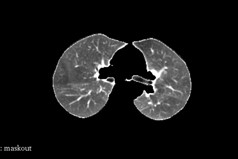

2.3 图像形态学

因为肺内部有许多纤维,所以看起来会有以下空洞(相对于肺部来说),要填补这些空洞,所以利用形态学里的闭操作(先膨胀,再腐蚀)。先膨胀肺部,将小的空洞填充,再腐蚀,恢复原来的大小。